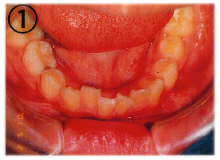

まず、矯正歯科治療とはただ単に「歯並びをきれいにする事」ではありません。

歯並びは「噛み合わせ」と「審美」に大きく影響します。

位置の悪い歯を正しい位置へ動かす事で、正しいキレイな歯並びや噛み合わせを作ります。

つまり、歯の正常な咀嚼機能を取り戻す事で“健全な身体と心をつくる”為の治療といえます。

当医院では「床(しょう)矯正」という矯正治療を実践しております。

基本的には永久歯を抜かず、顎を拡げて歯を並べる治療の事です。

床矯正で使用する装置は簡単に取り外せるので、虫歯や歯周病を患いにくく、清潔な口腔環境が保てます。